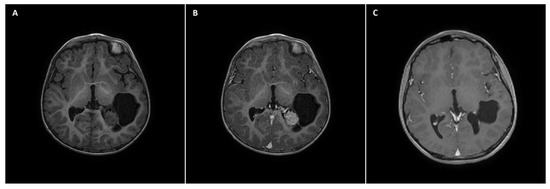

A 14-year-old female patient with recently diagnosed pertussis underwent a CT scan of her paranasal sinuses. Imaging data revealed a left-sided space-occupying lesion at the level of the thalamus. The patient underwent a subsequent brain MRI scan, which showed a cystic–solid 3 cm × 2.5 cm mass located within the anterior thalamus and basal ganglia on the left side (Figure 1A,B). On admission, the patient was neurologically intact. Due to the mass effect exerted by the tumor, the patient qualified for surgical tumor removal. Considering the eloquent location of the adjacent neural tissue, GTR was not achieved to preserve neurological function postoperatively. No surgery-related complications occurred. A postoperative MRI scan confirmed subtotal resection of the tumor (Figure 1C). The patient was discharged home without any neurological deficits. Subsequent pathological examination revealed ganglioglioma (WHO grade 1 tumor). The patient has been followed up for 111 months, with neither radiological regrowth nor the occurrence of focal neurological symptoms. However, the patient complained of periodic headaches, which are unlikely to be caused by the surgery.

Figure 1. A 14-year-old girl with right-sided thalamic ganglioglioma. (A) A preoperative axial non-contrast T1 MRI scan showing an isodose solid mass located within the right thalamus with an adherent cystic component, causing a mass effect and slight midline shift. (B) The preoperative axial postcontrast T1 MRI scan revealed a heterogeneous solid mass enhancement. (C) A postoperative axial postcontrast T1 MRI scan reflecting subtotal excision of the tumor, with reduced size of the cystic component, relieved mass effect, and no evident midline shift.